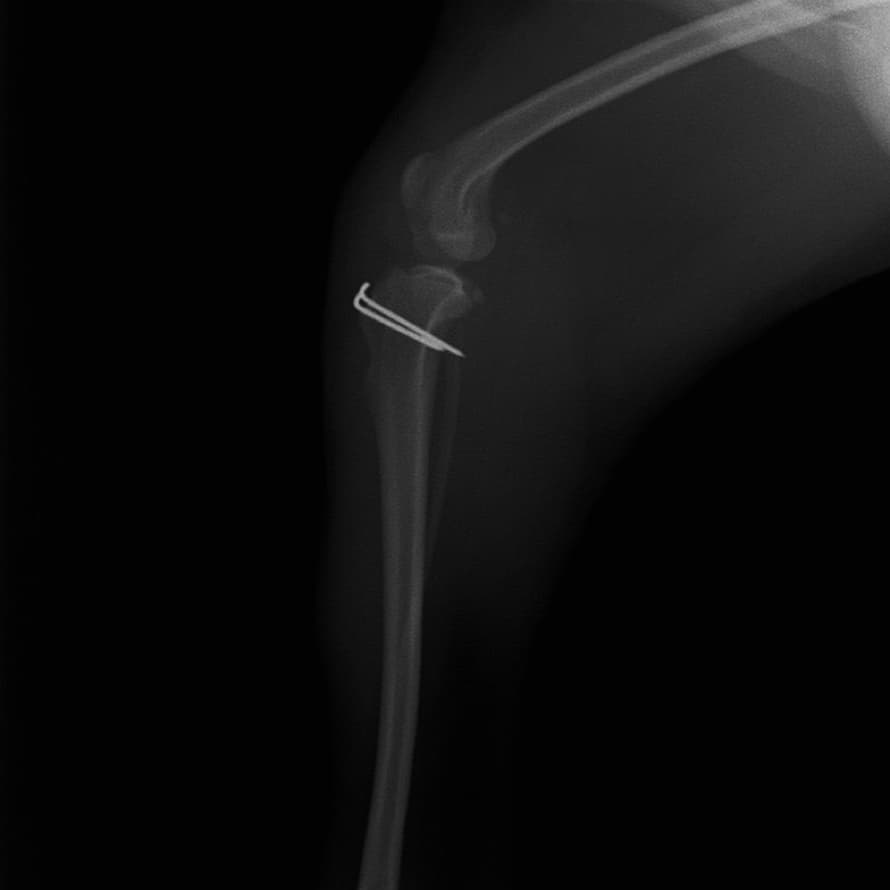

■ 症例20 ポメラニアン 8ヶ月 1.8kg

左右膝蓋骨脱臼 グレードⅢ

2ヶ月前から間欠的跛行が認められ、両膝の膝蓋骨脱臼整復術を行った。

手技は縫工筋及び内側広筋の解放、脛骨粗面の外側転位、滑車ブロック形造溝術、内外側関節包の縫縮を選択し実施した。

右側の膝蓋骨脱臼は上記手技で整復されたものの、左側はそれのみでは膝蓋骨が浮く様子が認められた。その為、PDS縫合糸にて膝蓋靱帯を1糸のみ縫合し、靱帯の縫縮を行った。

膝蓋骨脱臼は膝関節における膝蓋骨の内外側の脱臼と定義されるが、時として単純な内外の脱臼ではなく、膝蓋骨が大きく前方に浮き上がるように脱臼する場合がある。特にトイプードルやポメラニアンといった犬種に多く認められる。

内側脱臼に加えて前方への浮き上がりを矯正する為に、従来より脛骨粗面転移により膝蓋靭帯を外方と下方に引っ張り、固定する方法を選択する。膝蓋骨の前方への浮き上がりが軽度の場合は、従来法ではなく関節包の縫縮で対応していた。しかし、一部の症例で膝蓋骨の動きが悪くなり伸展機構が円滑に機能せずロボット様歩行になるケースがあった。

その為、膝蓋靭帯自体を縫縮する方法を採用した。この方法により、膝関節の伸展機構を妨げず膝蓋骨の軽度の浮きを矯正することが可能となった。

本症例の経過は良好である